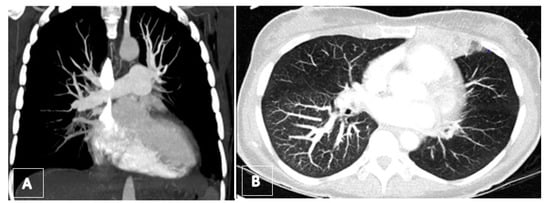

3.4. Computed Tomography Pulmonary Angiography (CTPA)